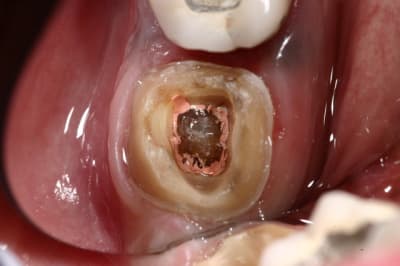

pour enfoncer le clou sur les tenons et autre inlay core

ne pas perdre de vue qu'un tenon = Rétention ... c'est tout !

Si on a de la rétention autrement, pas besoin de tenon...

Un tenon fragilise la racine et réduit l'étanchéité du traitement endo...

un cas comme on peut en faire souvent, d'endo couronne collée, exploitant le volume de la chambre pulpaire...

photo retrouvées :)

plus de place pour la ceramique, et plus de rétention dans l'endo que dans l'exo ;)